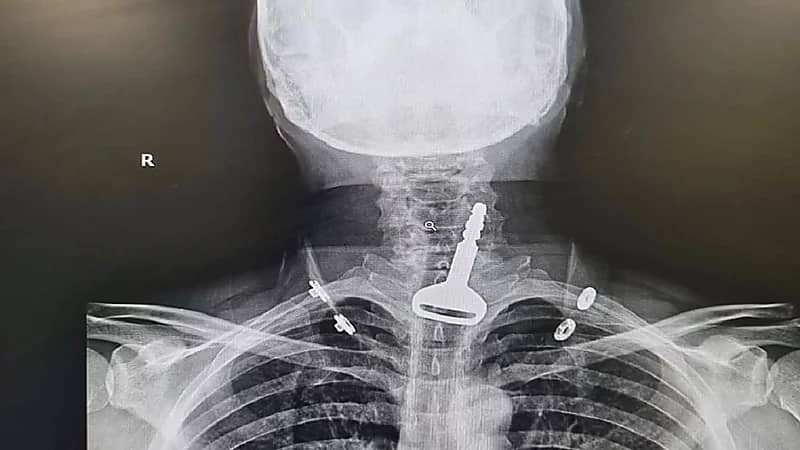

مفتاح سيارة كاد ينهي حياة أربعيني في القنفذة

نجاة طفل من الموت بأعجوبة بعد ابتلاعه “مفتاح” بالطائف